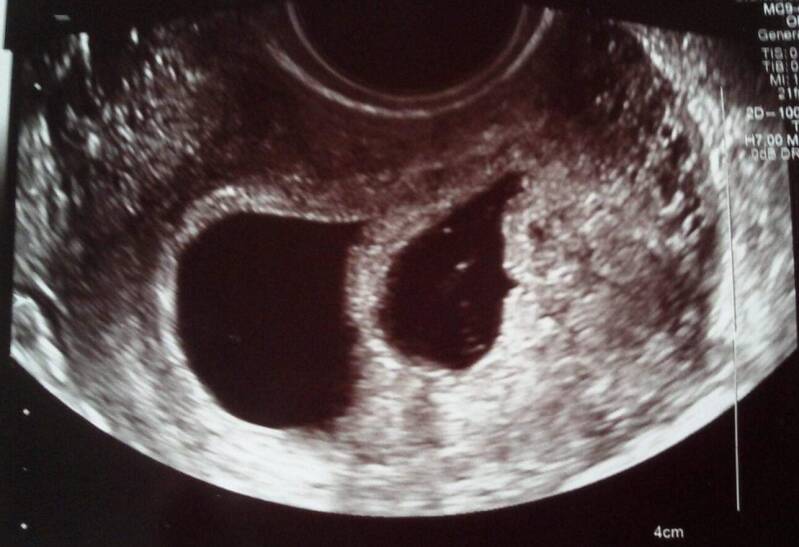

Ik moet met een volle blaas komen. De echo is dan duidelijker. De echoscopiste maakt een uitwendige echo. Op het eerste beeld denk ik twee holtes te zien. Een tweeling? Ik heb de taak van een volle blaas iets te serieus genomen. Mijn blaas is zo vol dat ik, tot mijn grote oplichting, mag gaan plassen. Eenmaal terug op de kamer wordt er een inwendige echo gemaakt. Al snel komt het goede nieuws. Twee kloppende hartjes! Wauw!